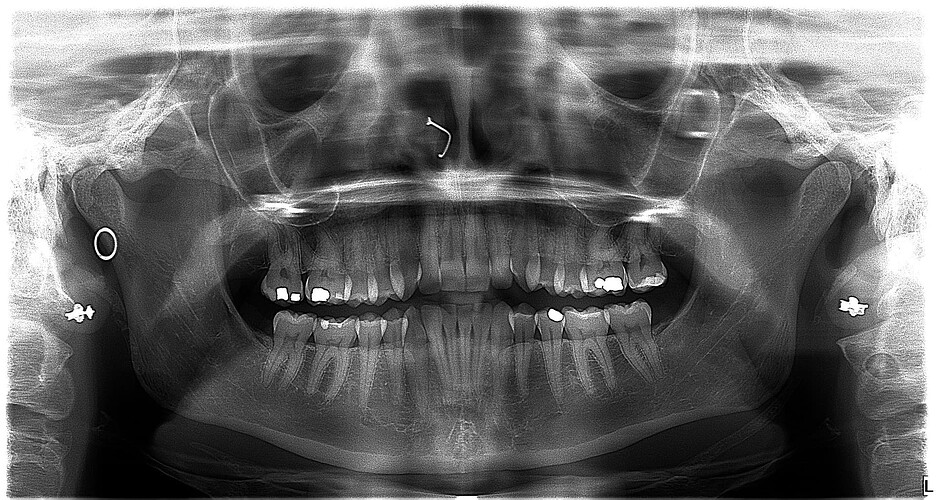

A referral has been sent by my dentist for a CBCT as she didnt see anything tooth or tmj related that would explain the pain. Ive attached a copy of my most recent panoramic xray in hopes any of you may have advise. I realize it may be hard to see, especially on a mobile device but hopefully you are able to zoom in. Thanks very much for any help or advise.

I’m not great with tech so I’m not able to label the image for you, but looking at it up close, it does look like there’s some calcification both sides ; on the left side of the image (your right), you can see some calcification between the 2 markers, and on the right side of the image it’s just to the left of the clip.

@Cin89 see attached annotated imaging.

Can visually see calcified stylohyoid ligament on both sides. On your left side your styloid is normal length, followed by a small section of normal stylohyoid ligament, but then followed by calcified stylohyoid ligament. On your right side, it appears to be one continuous chunk of calcification. Nonetheless, they pass C1, an area where the IJVs pass by, so it’s possible your IJVs are being compressed. A head and neck CT with contrast would be an important next step. It will allow the radiologist to measure the calcifications and assess for IJV compression. Unfortunately, unless there is contrast involved, a CBCT won’t show vascular compression.